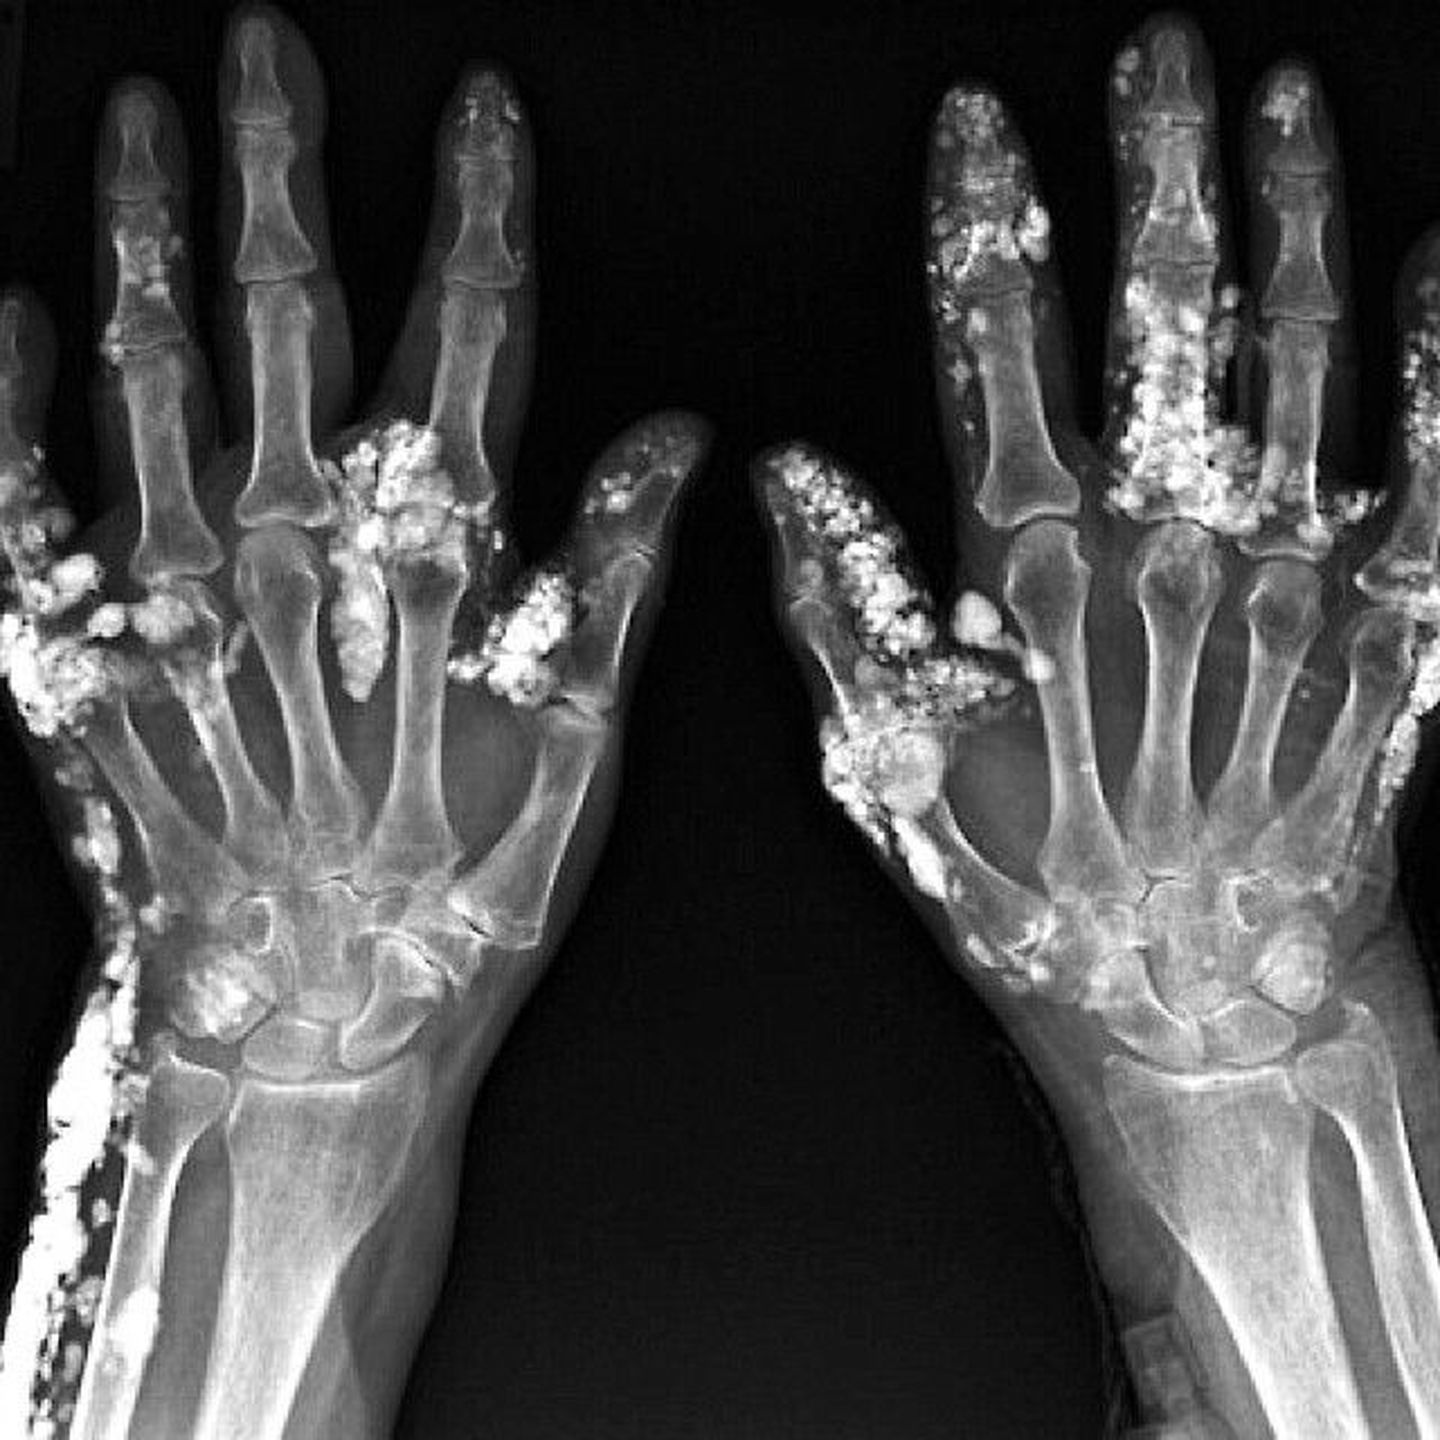

Calcinosis cutis refers to calcium deposition in the skin and soft tissues. It presents with subcutaneous white or pink nodules, often in the upper extremities. It is the first component of CREST syndrome, which includes Calcinosis cutis, Raynauds phenomenon, Esophageal dysmotility, Sclerodactyly and Telangiectasias. CREST syndrome is a type of systemic scleroderma where anti-centromere antibodies result in systemic inflammatory autoimmune connective tissue pathology.